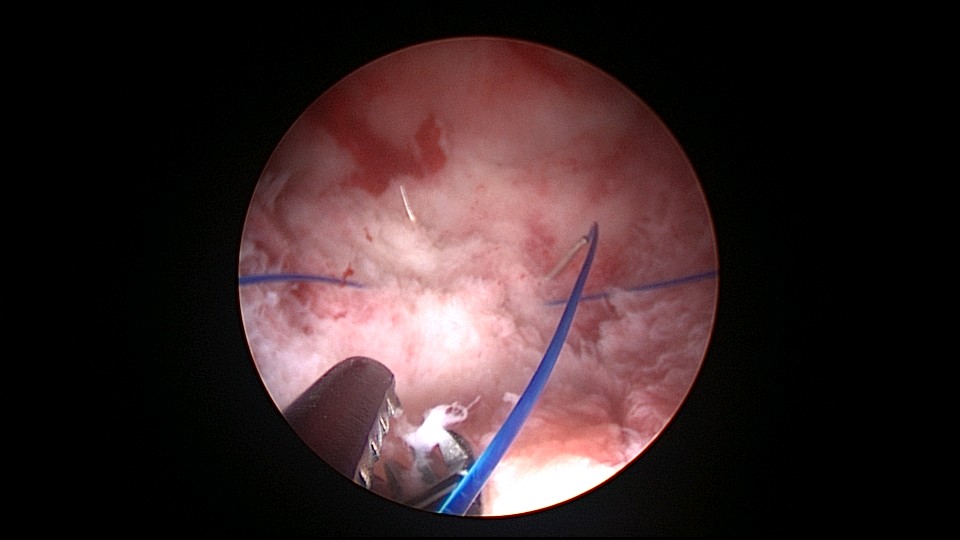

患者38岁,G4P2,剖宫产2次。2025年4月,停经40+天,计划外妊娠,要求终止妊娠并放置节育环,考虑终止妊娠后宫腔大,担心环移位或脱落,要求固定节育环。4-0不可吸收线将节育环缝合固定于宫腔上段后壁,缝合2针形成线圈固定节育环,没有打结推结。利用子宫肌层的卡压,缝合线圈不会自动松脱,形成有效固定,宫颈外口剪断线尾,留线较长,更利于固定。